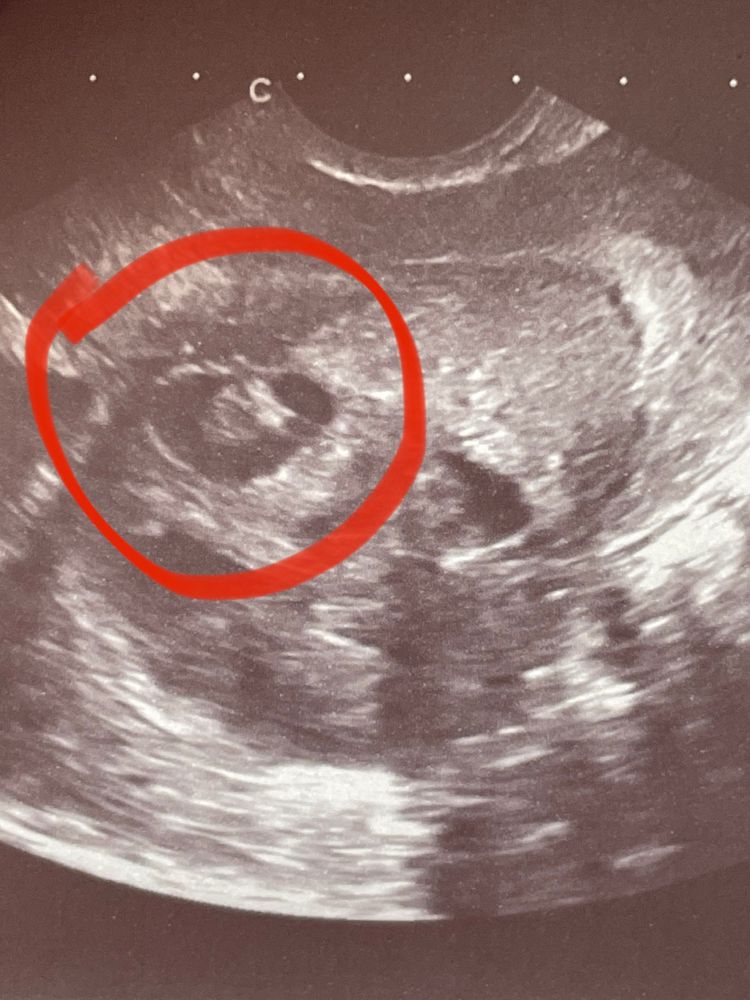

Кто разбирается в УЗИ??? Помогите расшифровать результаты фолликулометрии

А что в узи вам написали? Для беременности с разницей в месяц маловато. Тесты делали? Может зб какая?

Киста с пристеночный компонентом. Точно не беременность, потому что образование не в полости и даже близко не к полости, а в миометрии, во-вторых есть аналогичные кисточки, в третьих хгч был бы положительный, пока существует плодное яйцо. Лапара и гистера будут малоинформативны. Сделайте мрт органов малого таза. Я за эндометриоз/аденомиоз такой. Узловые формы бывают

Sofia, о беременности речи не идет, не о маточной не о внематочной. У Вас скорое всего овуляции не было в этом цикле. У Вас кисты обоих яичников, и киста внутреннего слоя матки, что и представлено на фото. Но киста имеет включение внутри, это не эмбрион. Все достаточно однозначно. Вам надо обратится к гинекологу для лечения кистозных изменений яичников и этой кисты.